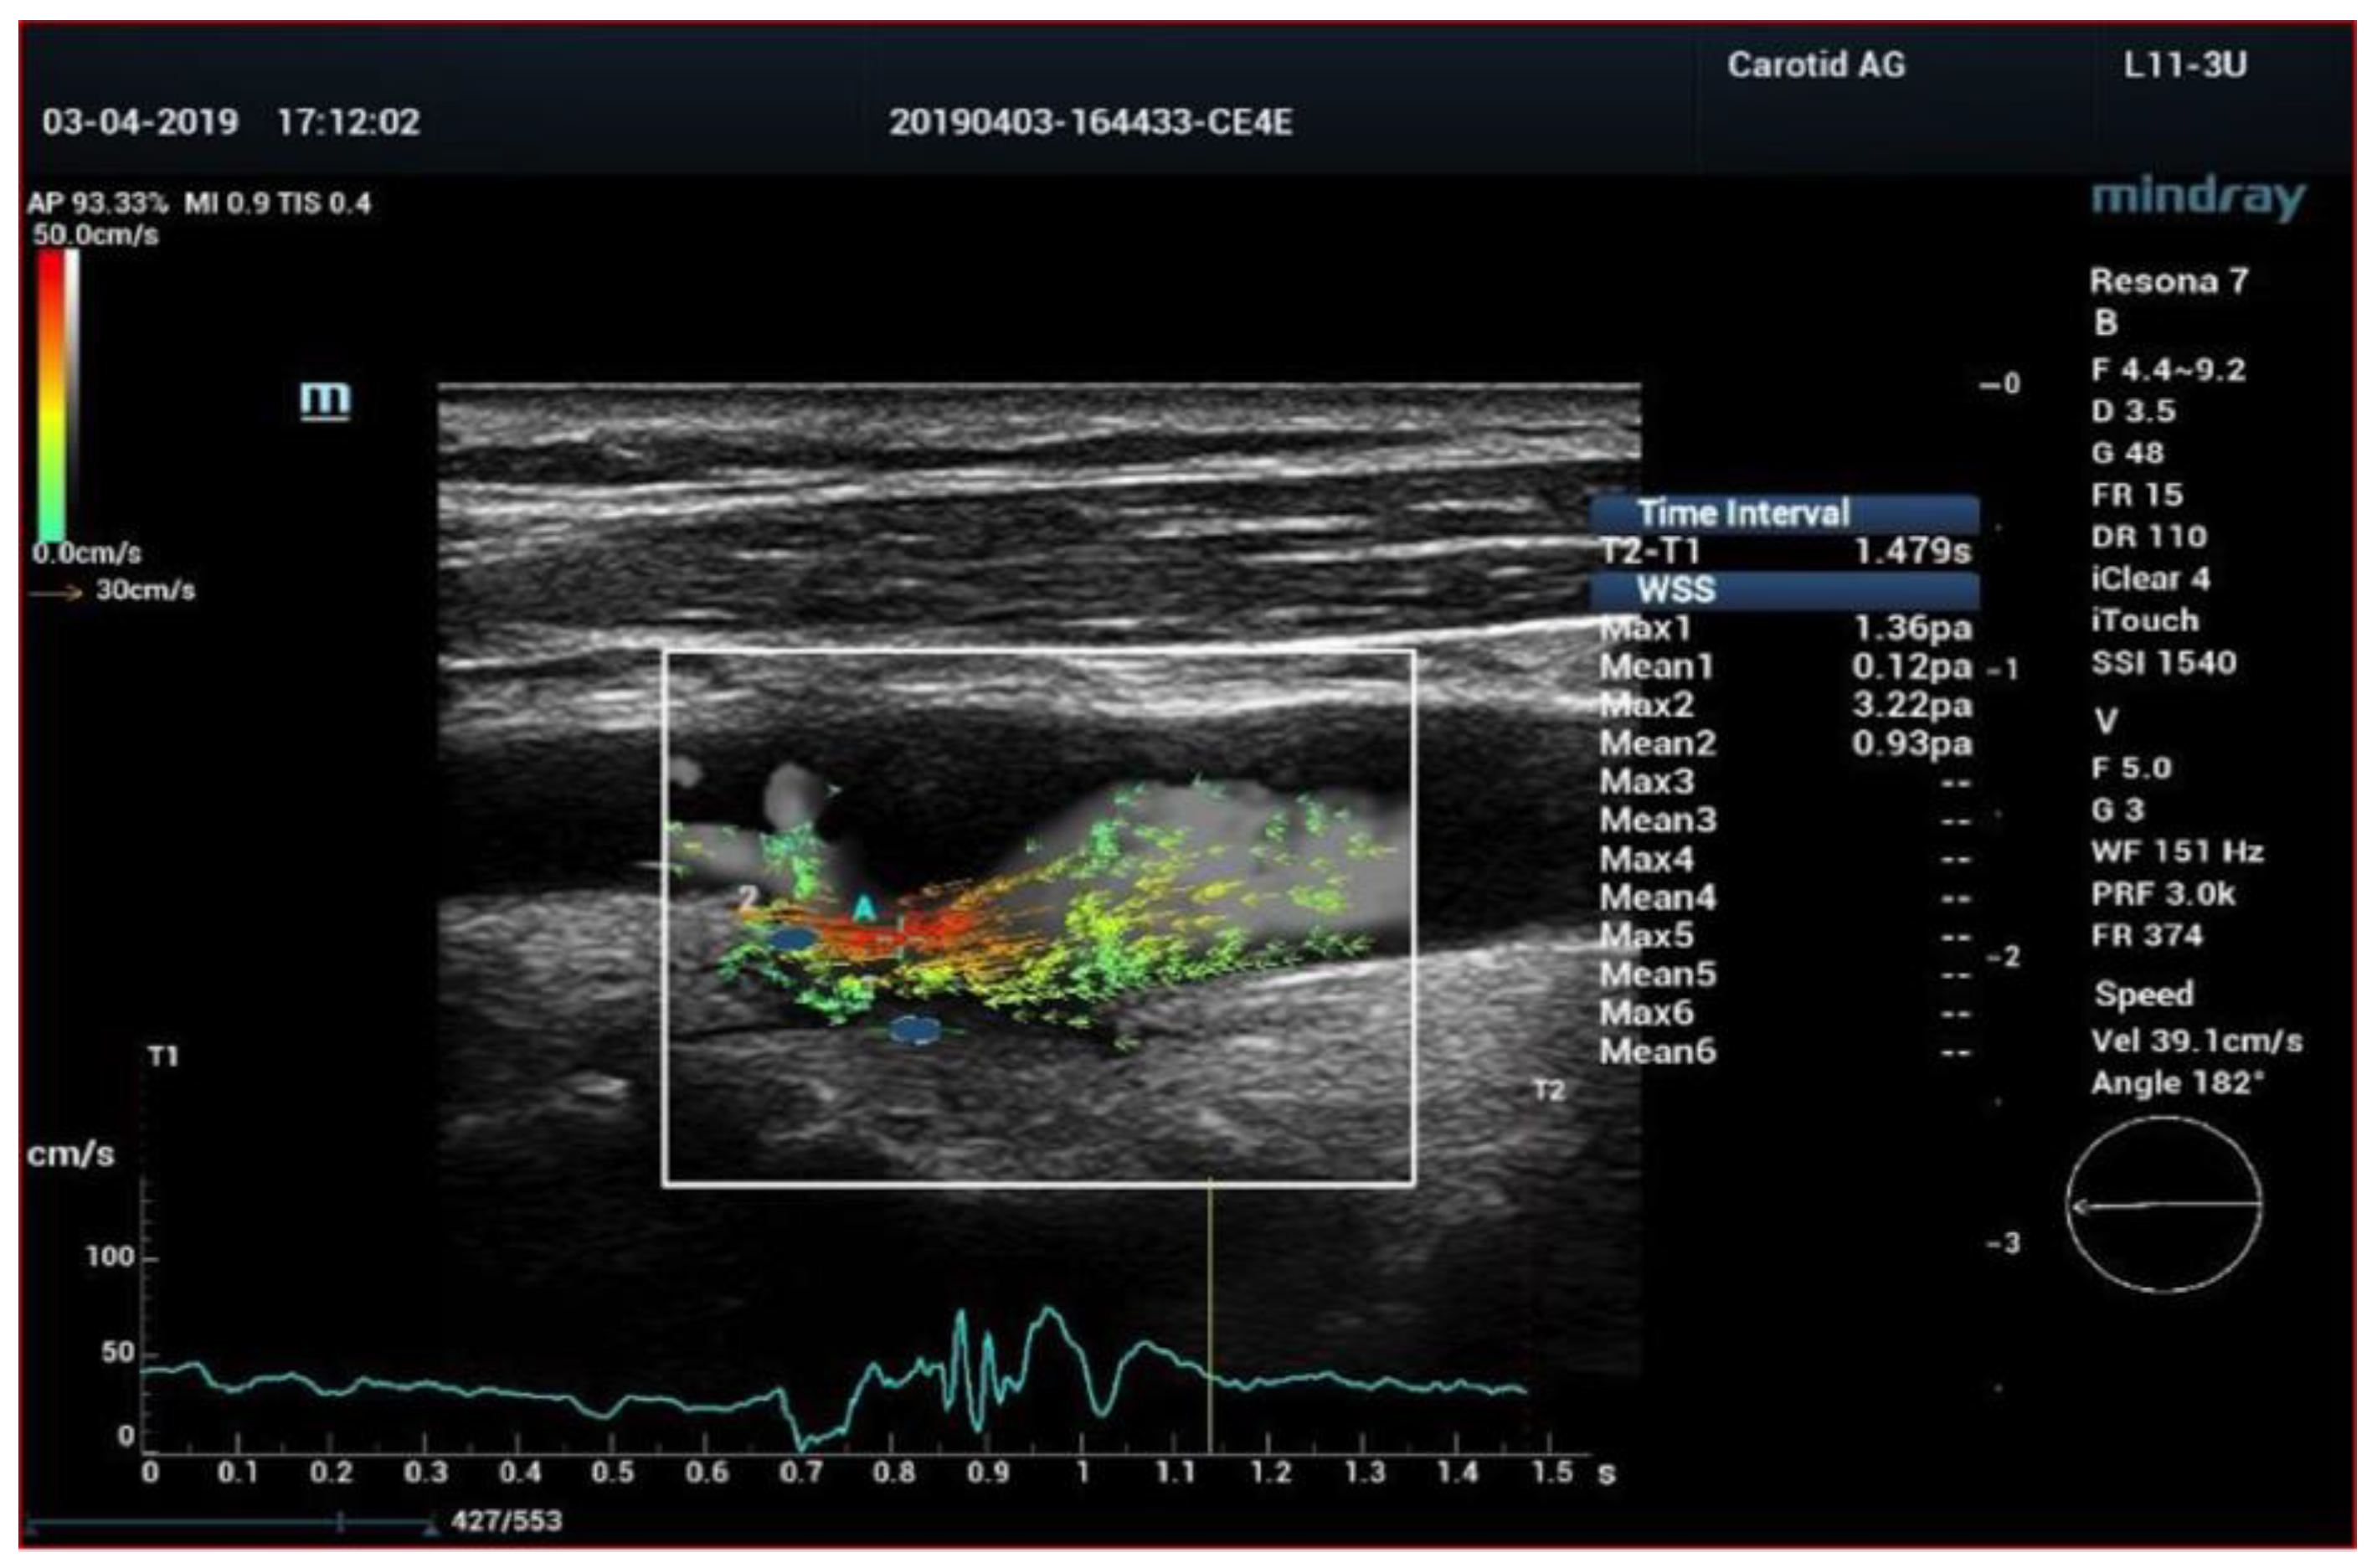

6. High Frame Rate Vector Flow (V-Flow) and 3D Arterial Analysis Ultrasound (3D-US)